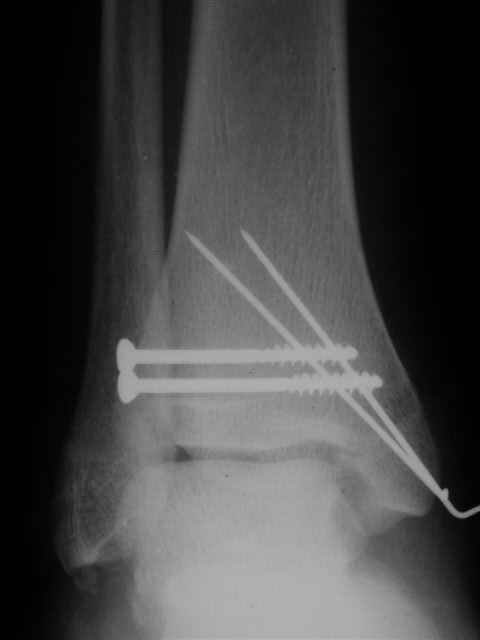

Re: открытый перелом мыщелков бедра, латерального

Я предупреждал, что ничего сверхъестественного. Каюсь, что одна из спиц прошла несколько дальше, чем нужно было, но главное - перелом стабилизирован и больной работает суставом в полном объёме, несмотря на представленную раннее травму коленного сустава.